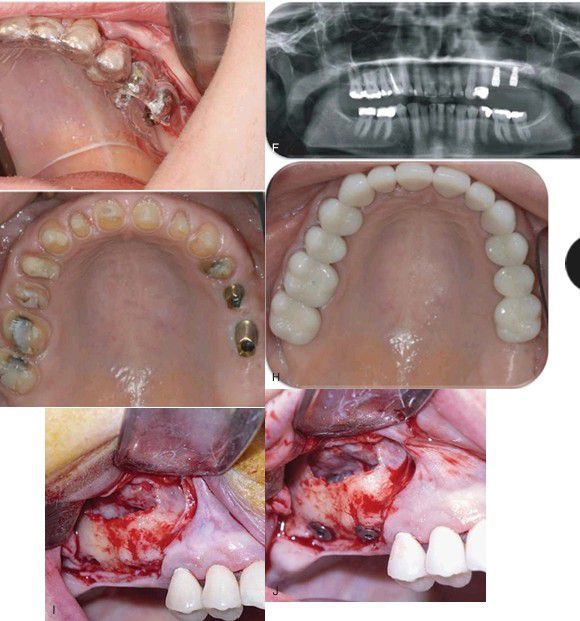

, cont’d (E) Implant placement using a surgical stent as a secondary procedure 5 months after the sinus augmentation was completed. (F) Postsurgical Panorex showing implant placement into the augmented left maxillary sinus. (G) Intraoral photo of prepared teeth and custom titanium implant abutments. (H) Final restorations in place. (I) Lateral bone window provides access; the sinus membrane is elevated and when enough native ridge is present for stability the implants can be placed at the time of sinus elevation. (J) Implants are placed through the native ridge and into the sinus.